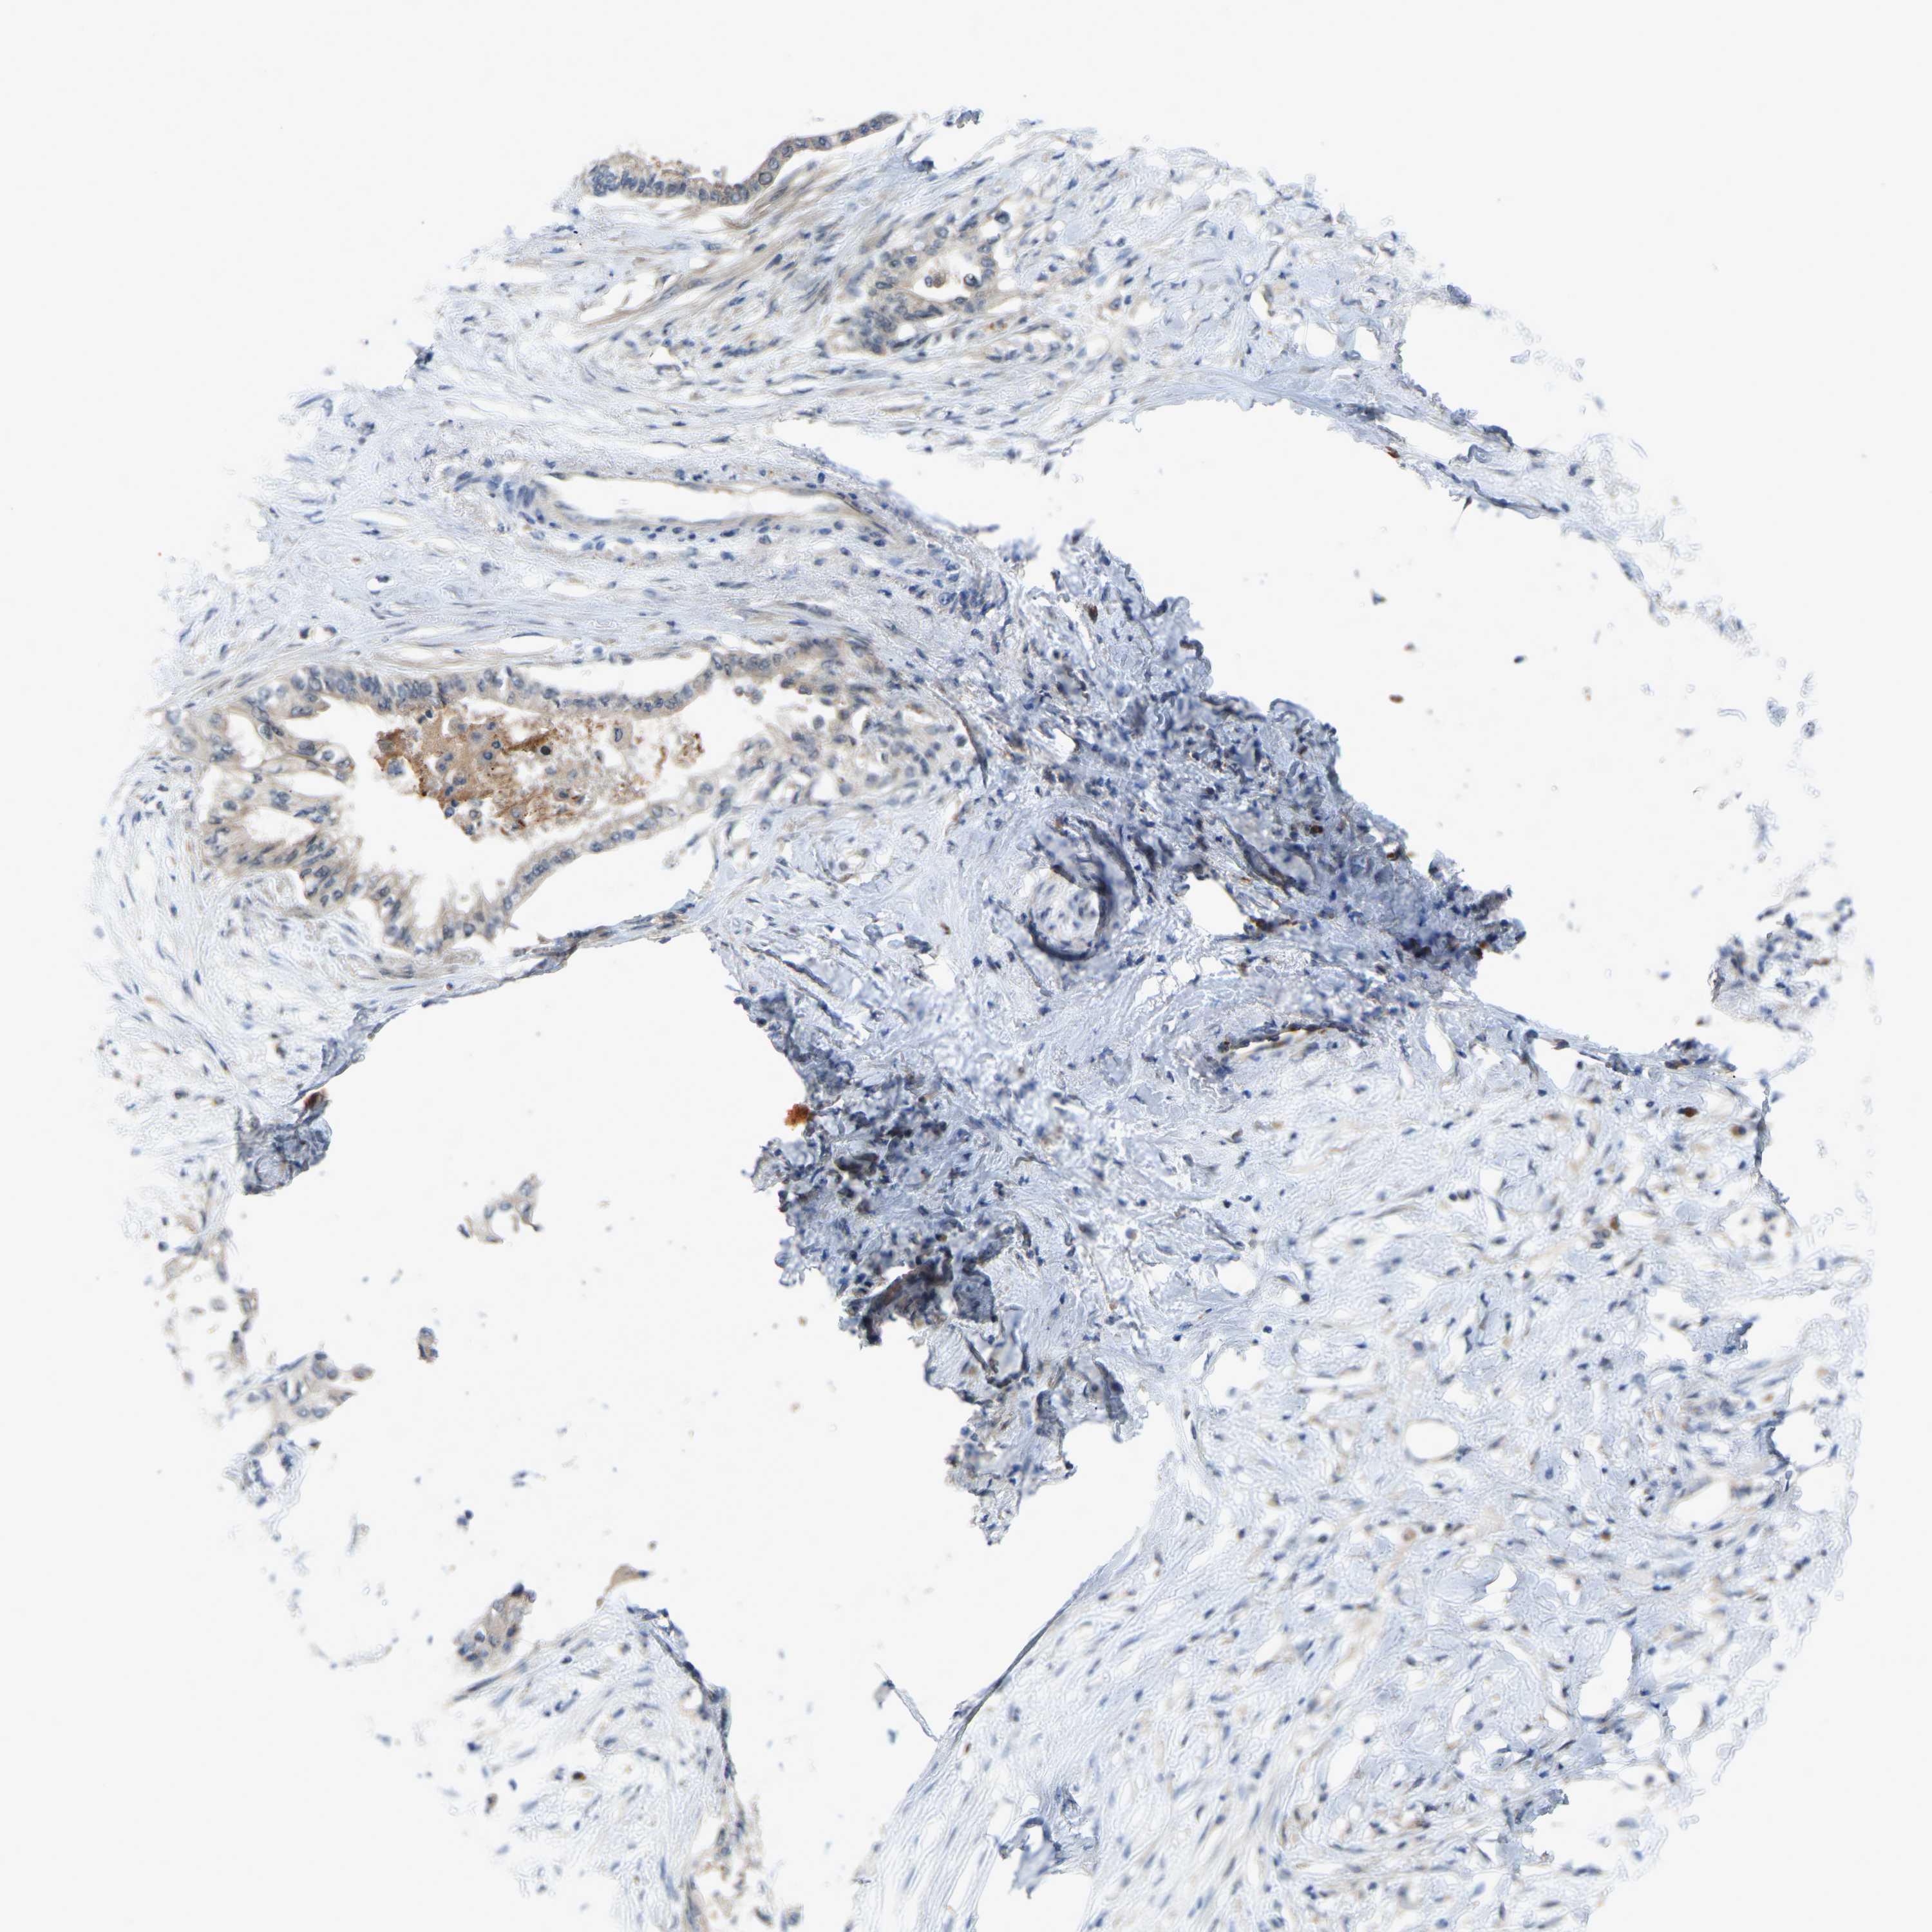

PANCREATIC CANCER - Protein expressioni

A mouse-over function shows sample information and annotation data. Click on an image to view it in a full screen mode. Samples can be filtered based on level of antibody staining by selecting one or several of the following categories: high, medium, low and not detected. The assay and annotation is described here.

Note that samples used for immunohistochemistry by the Human Protein Atlas do not correspond to samples in the TCGA dataset.

Antibody stainingi

Antibody staining in the annotated cell types in the current human tissue is reported as not detected, low, medium, or high, based on conventional immunohistochemistry profiling in selected tissues. This score is based on the combination of the staining intensity and fraction of stained cells.

Each image is clickable and will lead to virtual microscopy that enables deeper exploration of all samples and also displays staining intensity scores, fraction scores and subcellular localization as well as patient and tissue information for each sample.

Antibody HPA018840

Antibody HPA018909

Antibody CAB002684

Staining

High

Medium

Low

Not detected

Intensity

Strong

Moderate

Weak

Negative

Quantity

>75%

75%-25%

<25%

None

Location

Nuclear

Cytoplasmic/membranous

Cytoplasmic/membranous,nuclear

Adenocarcinoma, NOS

Adenocarcinoma, metastatic, NOS